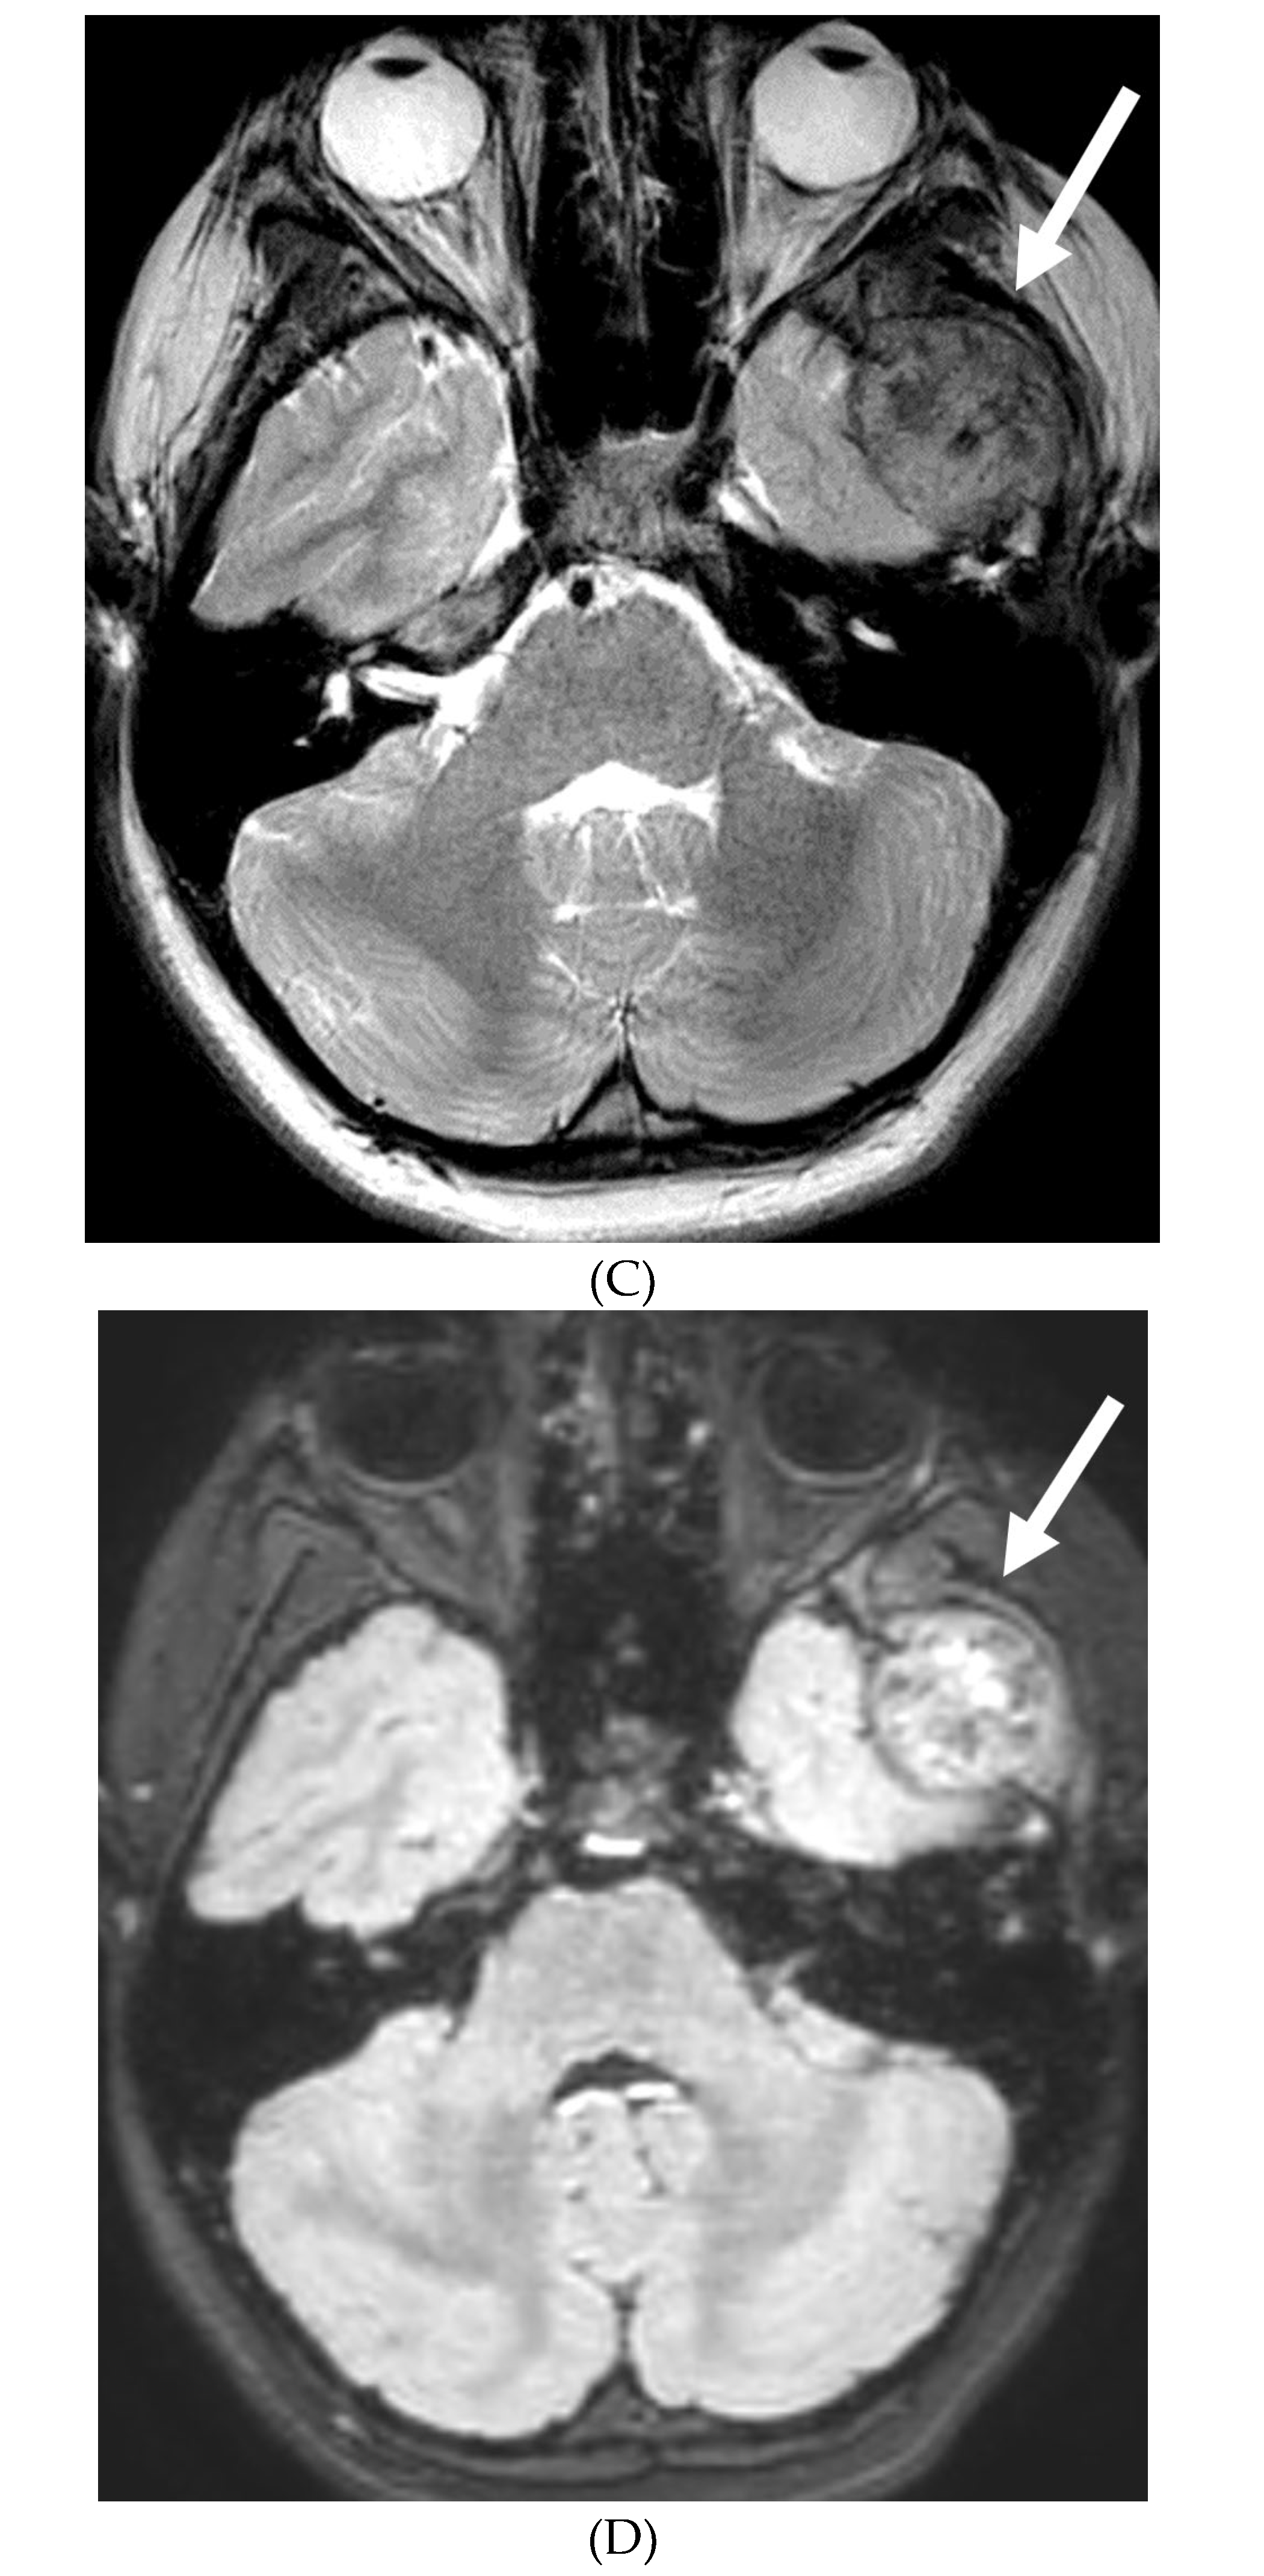

BACTERIAL MENINGITIS

- Vaswani AK, Nizamani WM, Ali M, Aneel G, Shahani BK, Hussain S. Diagnostic Accuracy of Contrast-Enhanced FLAIR Magnetic Resonance Imaging in Diagnosis of Meningitis Correlated with CSF Analysis. ISRN Radiol. 2014 Mar 20;2014:578986. PMID: 24977138; PMCID: PMC4062848. [CrossRef]

- Jaremko JL, Moon AS, Kumbla S. Patterns of complications of neonatal and infant meningitis on MRI by organism: a 10 year review. Eur J Radiol. 2011 Dec;80(3):821-7. Epub 2010 Nov 10. PMID: 21067879. [CrossRef]